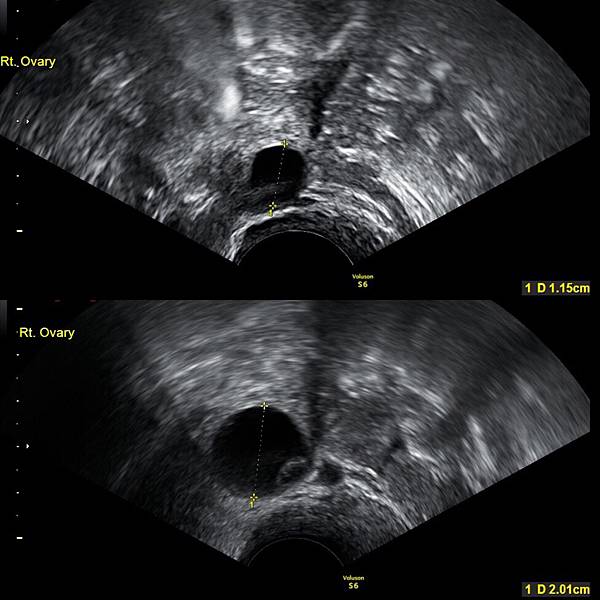

盼了一年多,用了不知道多少隻驗孕棒,始終沒有懷孕,決定求助醫生,醫生說我不是不孕只是不容易受孕,幫我照了卵泡大小,推論可能排卵的時間,和老公按時做功課,等結果。

上圖卵泡還太小,1.15cm